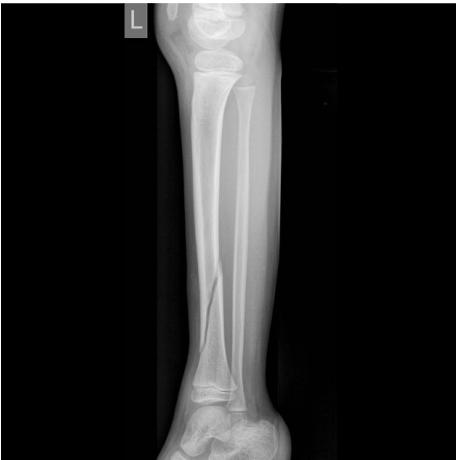

X-ray ap lat closed ,distal tibia extra-articular fracture, complete (two cortex), no articulation involvement, spiral (if two views appear broken), oblique (if one view) Oblique fracture, slight gapping (should be displaced if so), cortex appear normal, minimally displacement, angulation, rotation.